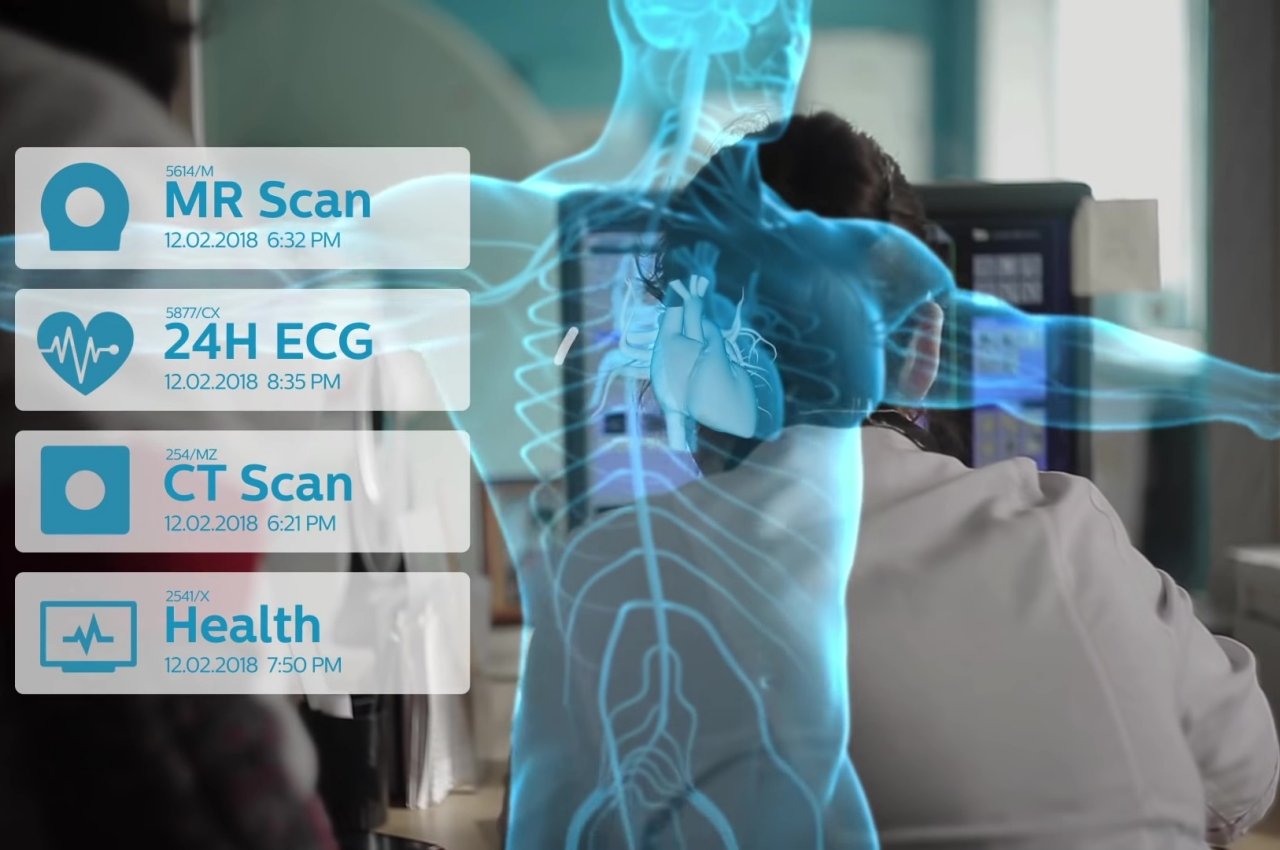

Gemelli digitali

La frase potrebbe evocare immagini orribili, in particolare di scene di iconici film horror degli anni '80, ma i gemelli digitali sono meno spaventosi o addirittura meno drammatici di quanto sembrino. In sostanza, un gemello digitale è praticamente una replica esatta di una cosa fisica, in questo caso, una persona, basata su dati del mondo reale. Questa replica può subire centinaia di modifiche simulate in pochi minuti o addirittura secondi che normalmente richiederebbero centinaia di anni in tempo reale.

In questa applicazione, l'apprendimento automatico e l'intelligenza artificiale sono al centro dell'attenzione su AR e VR, determinando i possibili risultati in base a fattori mutevoli. Per dirla senza mezzi termini, un gemello digitale potrebbe essere usato come una cavia virtuale, testando diversi farmaci e dosi, diverse procedure e diverse opzioni di trattamento per vedere quali avranno il miglior risultato possibile per un paziente. Tutto ciò può accadere in pochi secondi, magari anche nel bel mezzo di un'operazione.

I gemelli digitali possono essere usati su qualcosa di più dei soli umani, ovviamente. Lo stesso tipo di prove ed errori ad alta velocità può essere applicato allo sviluppo di medicine, all'analisi di virus, allo studio di animali e piante e qualsiasi altra cosa che possa essere risolta con alcune simulazioni. Ovviamente, guardare tutti questi dati come semplici figure e testo sarebbe noioso e persino doloroso, quindi i modelli 3D possono fare molto per visualizzare e comprendere i risultati di queste simulazioni. Punti bonus se puoi vederli anche nel Metaverso!

Designer: Philips